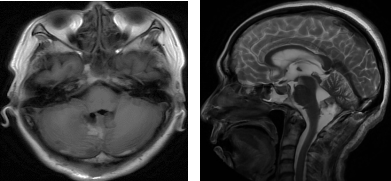

术后复查MRI 提示病变切除满意,脑积水缓解。

术后MRI影像

患者恢复顺利,临床症状完全改善。患者及家属对手术效果和我院医护的精心照顾,非常满意。